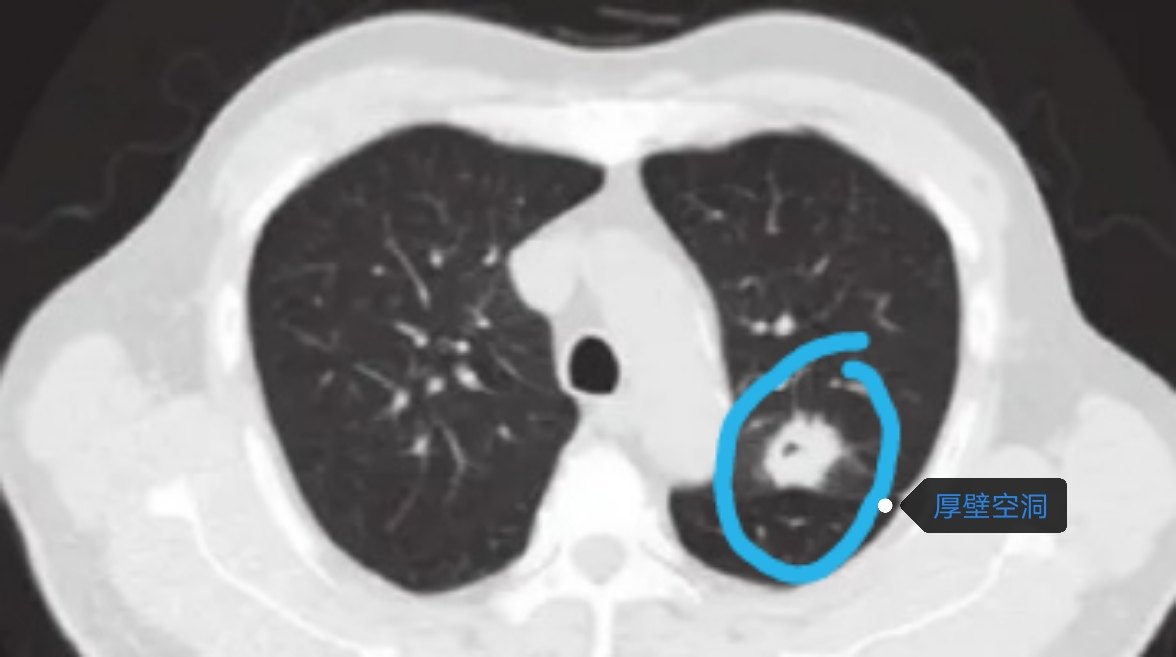

空洞型肺癌主要表现在CT上形成一个空洞,空洞壁厚薄不一,很薄的薄壁空洞看起来像肺大疱,厚壁空洞看起来像是肺炎实变后的眼睛?,空洞的形成机制仍不十分清楚,目前普遍认为厚壁空洞是由于肿瘤组织的缺血、感染及坏死导致肿瘤中央组织缺失后形成空洞 ;薄壁空洞的形成一般认为由于肿瘤细胞沿肺泡壁向细支气管生长或脱落堵塞细支气管,由于细支气管缺乏软骨,肿瘤细胞间接起到了活瓣作用,随着肿瘤细胞对肺泡壁的破坏以及肺泡腔内气体的逐渐增加,肺泡壁破裂,相互融合,形成薄壁空腔。但是,薄壁空洞的定义仍然没有统一的标准,目前多数学者将 4 mm 作为薄壁与厚壁的分界。

CT 上表现为磨玻璃结节成分时,病理类型多为原位腺癌、微浸润性腺癌或附壁为主型浸润性腺癌,这些肿瘤成分生长缓慢,代谢活性较低或肿瘤细胞密度较低,因此 PET-CT 中摄取相对较低,结果往往提示为阴性,当实性成分>8 mm 时,PET-CT 才会显示出摄取,因此, PET-CT 对于薄壁空洞型肺腺癌,尤其是实性成分较少、空洞体积较大的病变而言,检测意义不大,但厚壁空洞由于实性成分大,检查容易出现阳性结果。

厚壁空洞型肺癌穿刺取病理容易有阳性结果,但薄壁空洞型肺癌不一定会有较高的阳性率,要注意穿刺引起的气胸和种植转移,腔镜下切除快速冰冻病理可以取得比较准确的诊断,同时根据病理结果决定进一步切除范围。